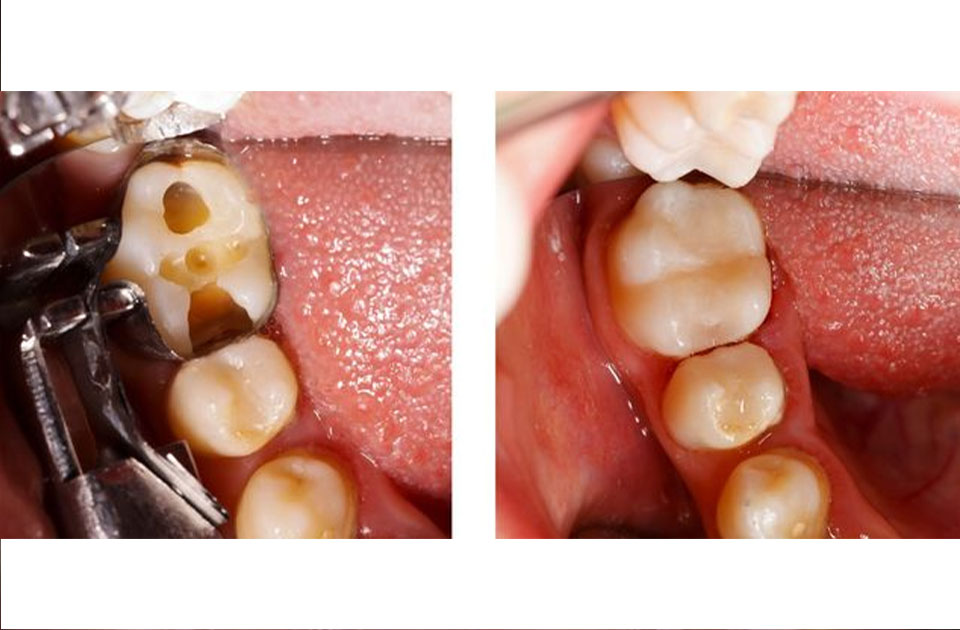

چیزی که بسیاری از افراد باید بدانند این است که اگر دندان های پوسیده و لثه هایی مشکل دار داشته باشید متاسفانه شما نمی توانید از کامپوزیت دندان استفاده کنید زیرا باید اول به درمان این مشکلات بپردازید و بعد از حل شدن مشکلات لثه و دندان های پوسیده خود می توانید از کامپوزیت دندان استفاده کنید .

پس افرادی که نمی توانند از کامپوزیت دندان ها استفاده کنند افرادی هستند که مشکلات لثه ای دارند و یا دندان های پوسیده شده دارند که ابتدا باید به درمان این مشکلات بپردازند و بعد از حل کردن این مشکلات می توانند با مشورت یک دندانپزشک با تجربه از کامپوزیت دندان استفاده کنند .